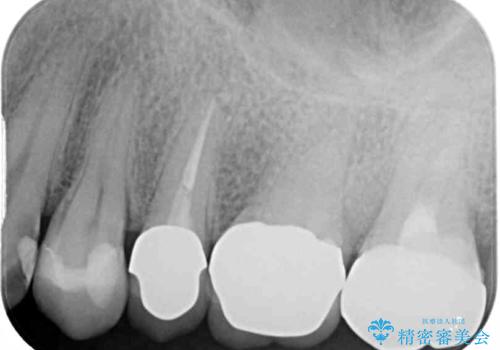

診査をしたところ、レントゲン写真よりとても大きなむし歯があることが分かりました。

虫歯が歯髄腔(神経の部屋)に達している可能性が非常に高かったため、炎症を起こしている神経組織を部分的に切除し、歯根部分の神経組織を保存する治療法が望ましいと考えられました。

処置開始前から神経組織を部分的に除去する可能性が高いことが分かっていたため、ラバーダムなどの環境を整え、無菌的環境下にて処置を進めて行きました。

虫歯は深くまで進行しており、歯冠部の神経から出血が認められました。神経を部分的に除去したところ出血が治まったので、生体親和性の非常に高いセメントにて充填し、仮封をしました。

後日状態を確認したところ、残された神経に異常がなかったため、セラミッククラウンにて補綴治療を行いました。